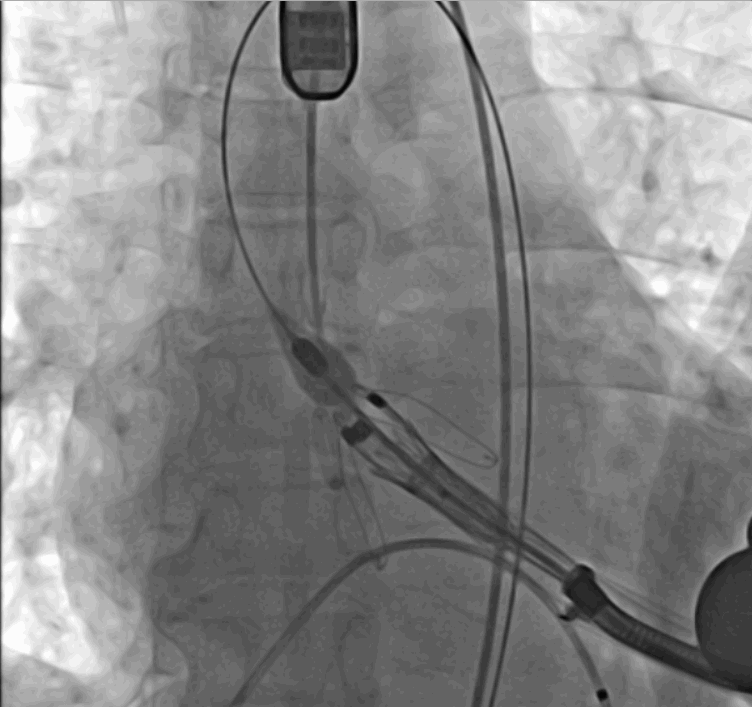

術(shù)中瓣膜釋放過程

手術(shù)采用經(jīng)心尖入路,對患者進(jìn)行全麻后,在左側(cè)心尖處做3-4cm微創(chuàng)手術(shù)切口,在DSA及超聲引導(dǎo)下手術(shù)順利完成。從導(dǎo)入器械到完成瓣膜置入,僅耗時(shí)約10分鐘。術(shù)后即刻主動(dòng)脈瓣返流程度由術(shù)前大量返流轉(zhuǎn)為消失,患者于導(dǎo)管室拔除氣管插管,次日由ICU轉(zhuǎn)入普通病房。